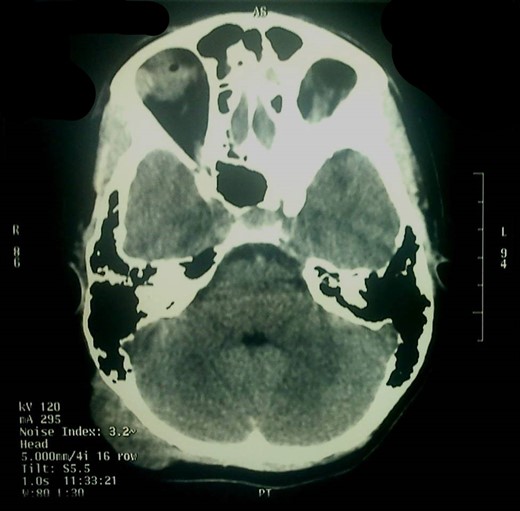

Α 12-year-old girl presented to us with a painless tumefaction on the right suboccipital region evolving for 5 months. Clinical examination did not reveal any other important symptoms or signs. Various explorations carried out, in particular, X-rays (Fig. 1), CT scan with intravenous contrast medium (Figs 2 and 3) and imagery by magnetic resonance with intravenous paramagnetic contrast.

MRI showed an encapsulated spindle formation in the region of the soft tissues of the right suboccipital region (Fig. 4). It was primarily located in the subcutaneous tissues, with a broad attachment to the outer table of the diploe, which appears to be thinned. It had mainly intermediate signal on T1W and T2W images, combined with some areas of high signal on T2 and low signal on T1. After the intravenous injection of the contrast, it showed inhomogeneous uptake.

The CT scan showed that there was only thinning of the bone without erosion or intracranial extension of the mass. There were no signs of calcification, and there was a mild and inhomogeneous uptake of the contrast.